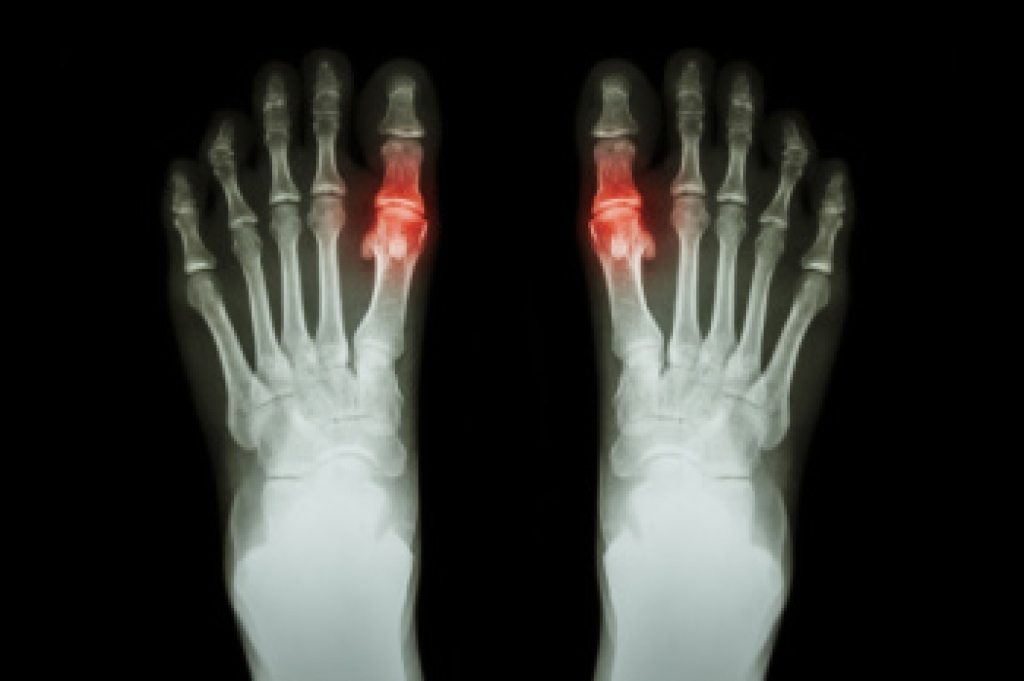

Morton's neuroma is a painful foot condition that commonly affects the areas between the second and third or third and fourth toe, although other areas of the foot are also susceptible. Morton’s neuroma is caused by an inflamed nerve in the foot that is being squeezed and aggravated by surrounding bones.